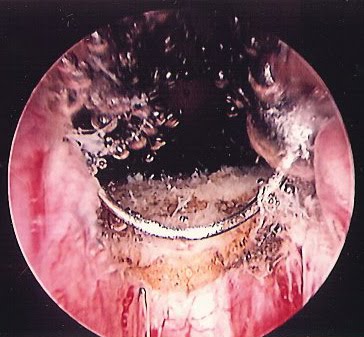

La TURP permite el retiro del tejido a través de un aparato especialmente diseñado denominado resector, el cual es introducido a través de la uretra. El resector se ubica a nivel del tejido prostático, para posteriormente retirar dicho tejido en fragmentos.

El procedimiento es monitorizado mediante vídeo, lo cual permite obtener imágenes en tiempo real, aumentando de esta manera el campo visual del cirujano, mejorando la efectividad del procedimiento.

Luego de ser retirado el adenoma, el urólogo realiza una inspección rigurosa de la cápsula restante, para constatar la adecuada hemostasia y de esta manera evitar un sangrado importante.